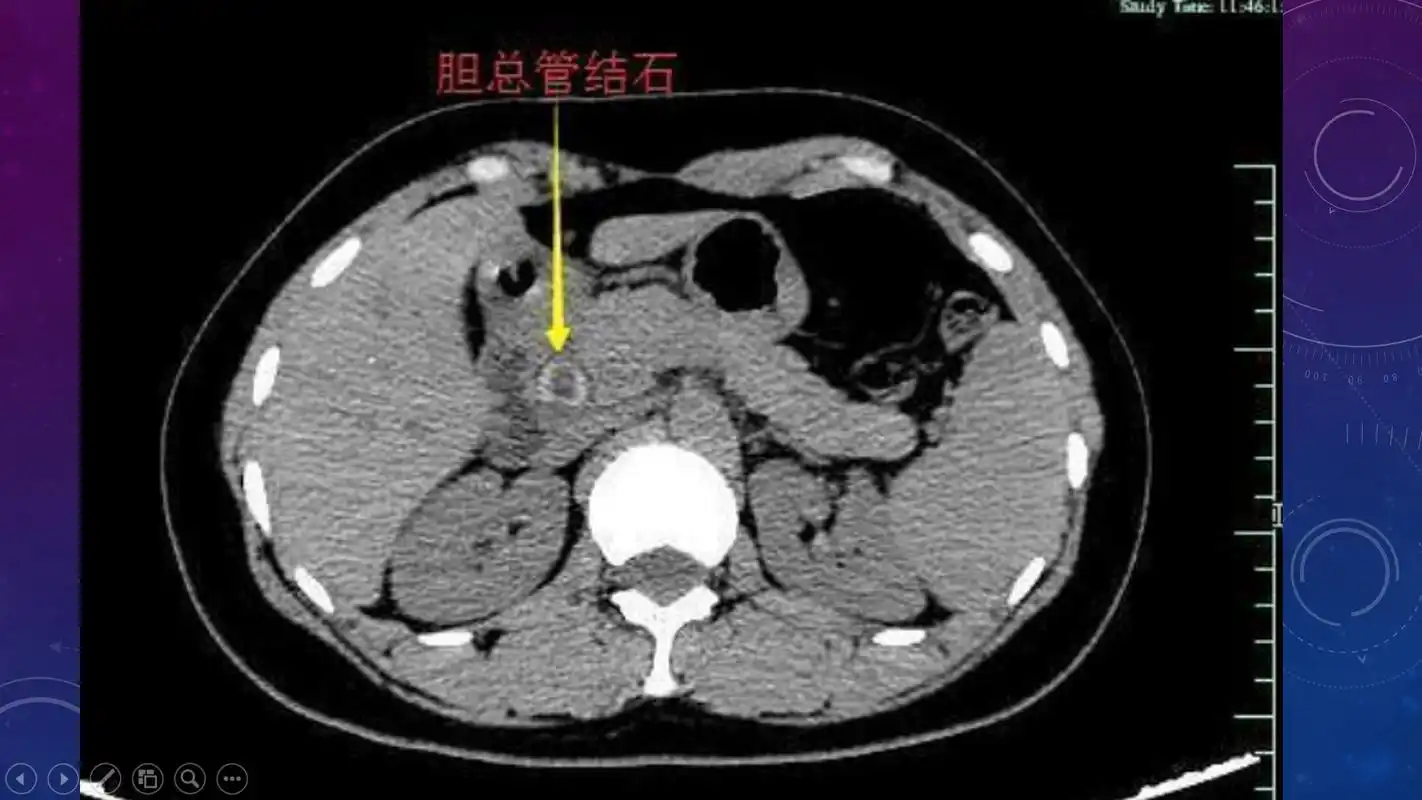

急腹症影像:胆道结石ct表现!